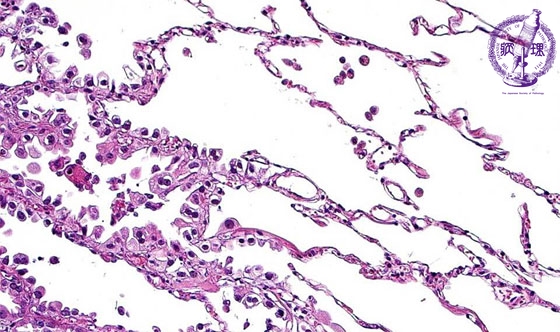

- ★(17)Non-small cell lung carcinoma(adenocarcinoma)

Microscopic view (HE stain, high power view): At the periphery of adenocarcinoma, carcinoma cells replace the lining alveolar cells without destruction of the underlying structure. The border between carcinoma cells and non-neoplastic alveolar cells (dotted line) is clear.